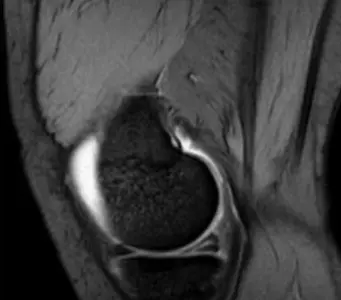

What pathology is seen in this MRI of an 18-year-old male who twisted his knee?

- Posterior horn meniscal tear

- Bucket-handle meniscal tear

What is the significance of the double PCL sign?

- Indicates bucket-handle meniscal tear